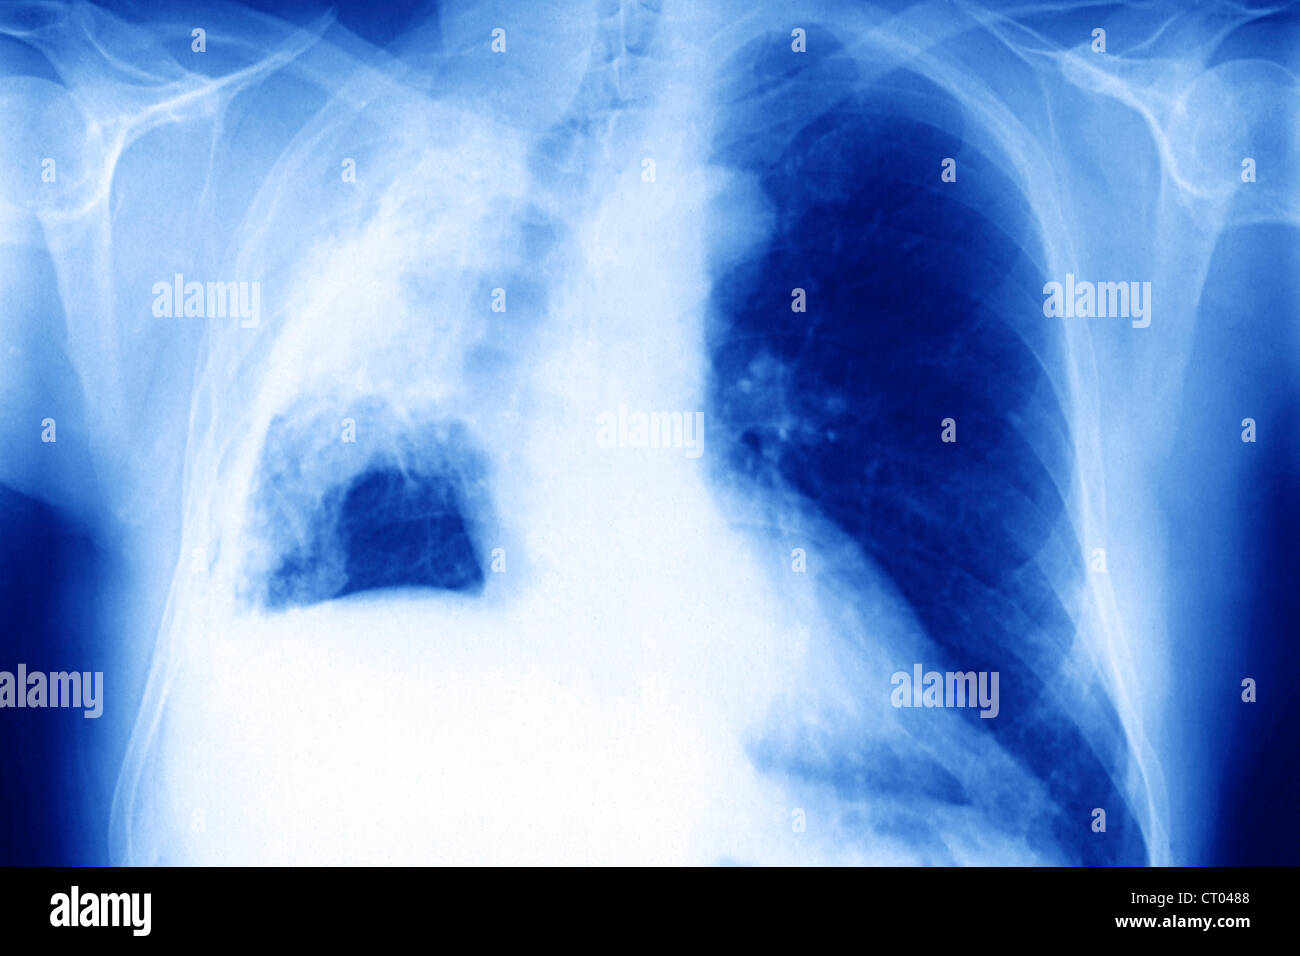

Knoten oder Flecken:

Dies sind die häufigsten Anzeichen für Lungenkrebs auf einem Röntgenbild. Ein Knoten ist eine runde oder ovale Verdichtung, die in der Lunge sichtbar ist. Er kann klein oder groß sein, scharf oder unscharf begrenzt sein. Flecken sind weniger klar definiert und können auf eine Entzündung oder andere Lungenerkrankungen hinweisen, aber auch auf Krebs.

Stell dir vor, du schaust auf eine Landkarte und siehst plötzlich einen dunklen Punkt, der da nicht hingehört. Das könnte ein Knoten sein. Die Größe, Form und Klarheit des Punkts geben Hinweise darauf, ob es sich um etwas Ernstes handelt.

Pleuraerguss:

Die Pleura ist eine dünne Membran, die die Lunge umgibt. Ein Pleuraerguss ist eine Ansammlung von Flüssigkeit zwischen den beiden Schichten der Pleura. Dies kann durch Krebs verursacht werden, aber auch durch andere Erkrankungen. Auf einem Röntgenbild erscheint der Erguss als eine Verschattung im unteren Bereich der Lunge.

Stell dir die Lunge in einer Art "Wassertasche" vor. Wenn sich zu viel Wasser in dieser Tasche ansammelt, wird die Lunge zusammengedrückt und es wird schwerer zu atmen. Das Röntgenbild zeigt diese Flüssigkeitsansammlung.

Atelektase:

Atelektase bedeutet, dass ein Teil der Lunge zusammengefallen ist. Dies kann durch einen Tumor verursacht werden, der einen Bronchus blockiert und die Luftzufuhr zu einem Teil der Lunge verhindert. Auf einem Röntgenbild erscheint die Atelektase als eine Verschattung, oft begleitet von einer Verschiebung des Mediastinums (der Raum zwischen den Lungen).